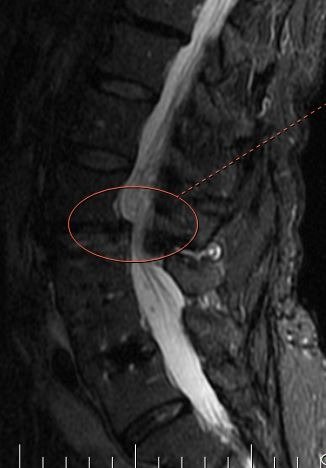

The MRI shows the side view of the low back [lumbar spine] showing the narrowing of the spine where the fluid seems to be cutting off in the middle of the lumbar spine [marked with an ellipse].

As we age, our spine develops arthritis and degeneration of the disc and adjacent joints. As arthritis develops, the area available for the nerve roots diminishes. The pressure on the nerve roots can cause both back and leg pain.

If conservative measures fail, lumbar decompression allows removal of the arthritic elements and taking away the pressure on the lumbar nerve roots.